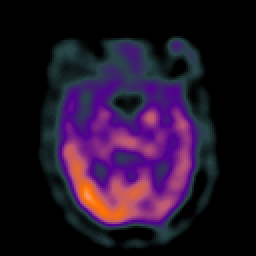

Subacute Stroke overlay -- Slice #10

[Home][Help][Clinical] Slice 10